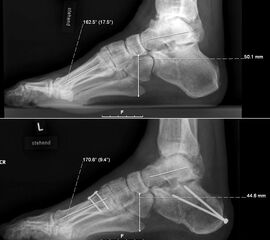

Dorsalflektierende Osteotomien des medialen Mittelfuβes (Abb. 6 – 9, Video 4)

• Erhöhter lateraler Talo-Metatarsale I Winkel (Meary-Winkel) als Ausdruck des plantarflektierten medialen Mittelfuβes, insbesondere im "forefoot driven hindfoot varus" (positiver Coleman block Test).

Die reduzierte Steilstellung des 1. Strahls wirkt sich positiv auf den Rückfuβ varus und den Vorfuβ adductus aus. Auch die relative Dorsalflexion des Talus in der Sprunggabel mit anterioren OSG-Impingement und verringerter OSG-Dorsalflexion wird verbessert.

Generell wird die dorsalflektierende MT I Osteotomie (Abb. 6 und 7) nicht isoliert ausgeführt, sondern ist Teil der gesamten Hohlfuβ-Korrektur. Beim absolut flexiblen Hohlfuβ ist sie gelegentlich zusammen mit einem Peroneus longus auf brevis oder einem Release der Plantarfaszie ausreichend. Diese Osteotomie ist einfach durchzuführen und hat eine geringe Pseudarthroserate.

Eine ähnliche dorsalflektierende Osteotomie des Os cuneiforme mediale (reversed Cotton Osteotomie, Abb. 8 und 9), ebenfalls mit Entnahme eines dorsal basierten Knochenkeils, ist effektiver im Ausmass der Korrektur, jedoch oftmals wegen der Insertion des kräftigen Lisfranc-Ligaments nur schwierig zu schliessen.